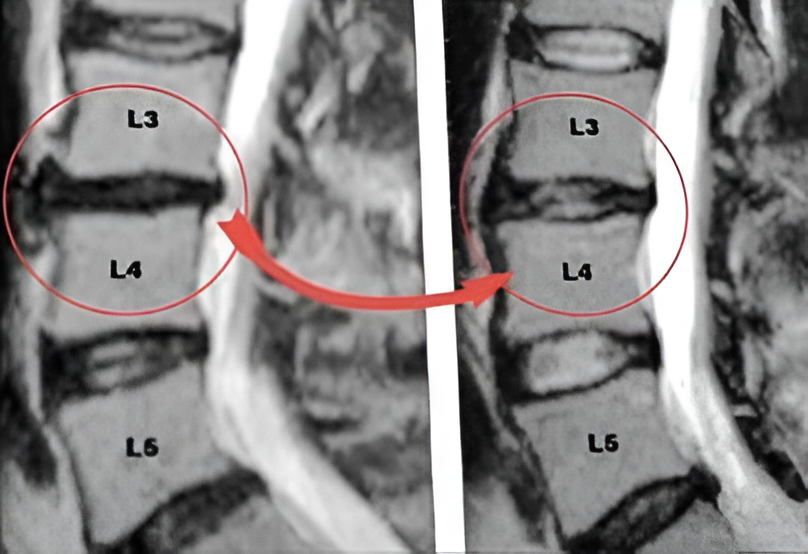

Symptoms from a bulging disc come on slowly over time. You may have neck or back pain, with tingling, numbness or weakness in your arms, hands, legs or feet.

A bulging disc slowly presses on nerves, causing gradual neck or low back pain.

Pain may radiate to arms/hands (cervical) or buttocks/legs/feet (lumbar) – often with tingling or numbness.